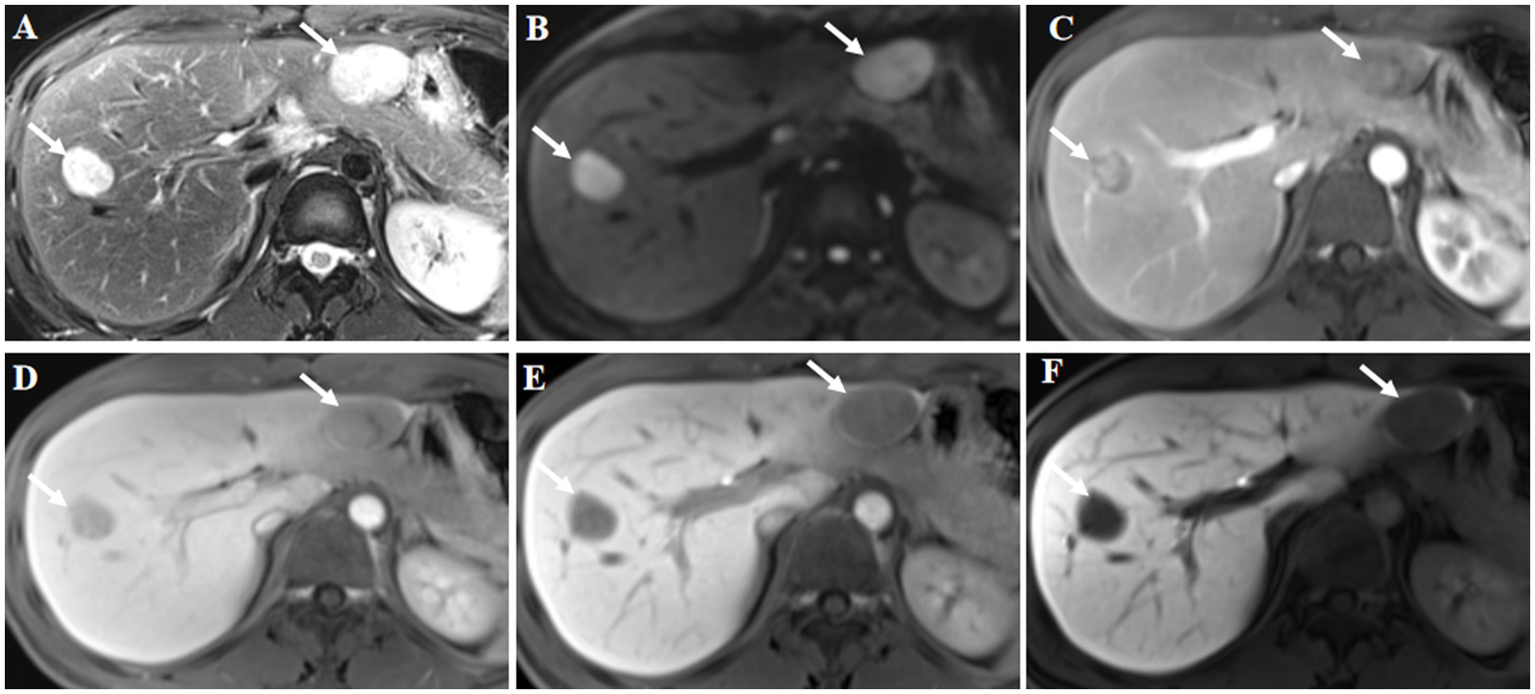

Figure 2

Gd-EOB-DTPA magnetic resonance imaging (MRI) findings. The lesions were located in liver segments V and III, and showed high signal intensity on axial T2-weighted imaging (A, arrow). Diffusion weighted image showed diffusion restriction (B, arrow). Contrast-enhanced MRI showed inhomogeneous enhancement of the lesions at arterial phase (C, arrow). The signal intensity of the lesions was lower at the portal phase (D, arrow) and delayed phase (E, arrow) compared with the surrounding liver parenchyma. Hypointensity was noted in the hepatobiliary phase at 30 min post-injection (F, arrow). Hepatocellular carcinoma was considered based on the findings of the magnetic resonance imaging.